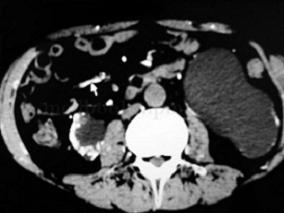

1小时条评论【病例资料】 患者男性,22岁。 主诉:发现腹部肿物1年余。 现病史:患者1年前发现腹围增大,似可触及肿物,未予诊治。近1年来,腹围增大渐加重。患者无腹痛、腹胀、恶心和呕吐,无便秘和腹泻等排便症状,也无尿频、尿急和排尿困难等排尿症状。1周前于我院行超声...